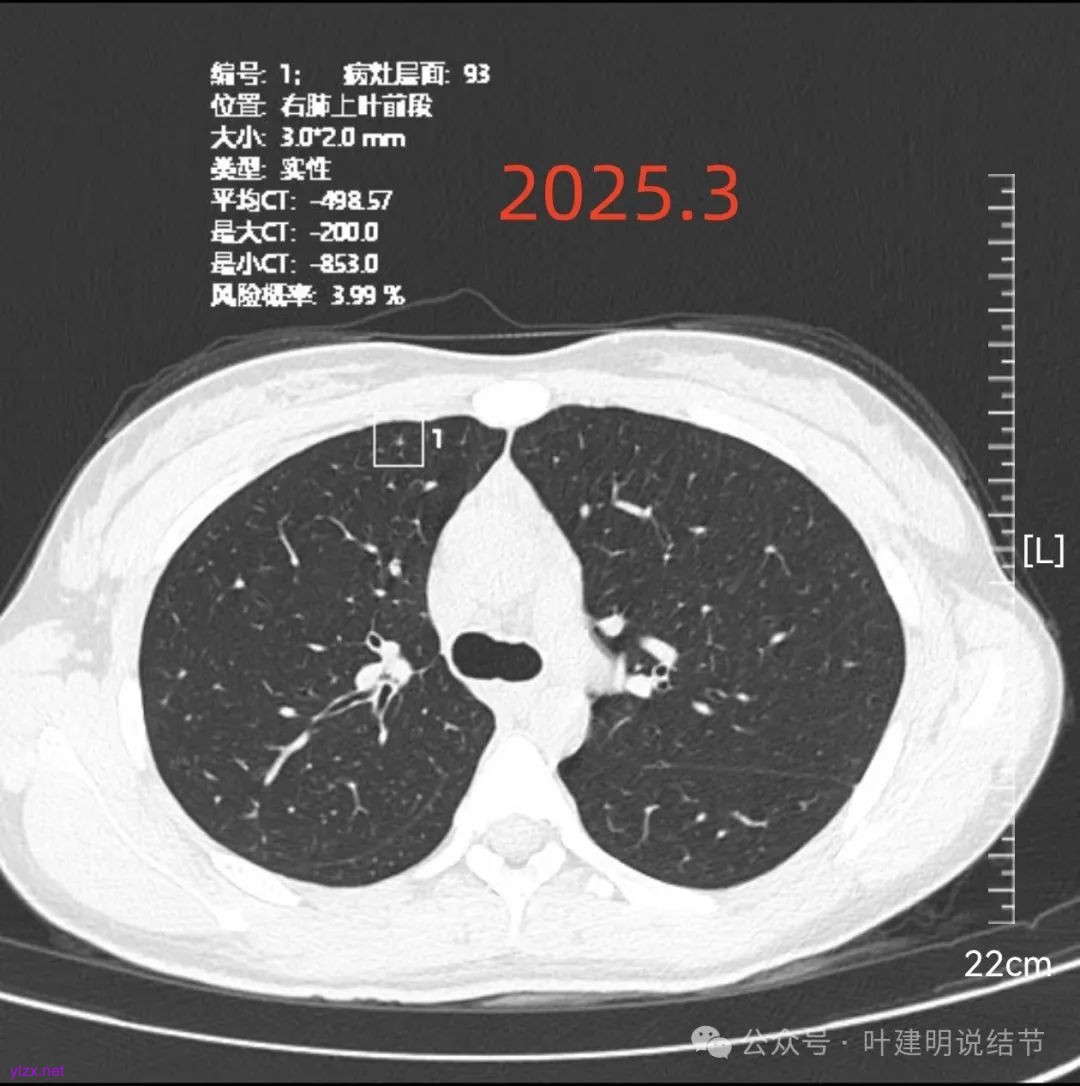

再看2025年3月的影像:

各病灶均无明显吸收好转,但显然也说不上有明显进展。所以基本上要考虑是肿瘤范畴的(包括肺泡上皮不典型增生或肺泡上皮增生)。但危险性显然不算高,至少近2年了没有什么进展,即使病灶6最厉害的也是纯磨密度伴空腔。